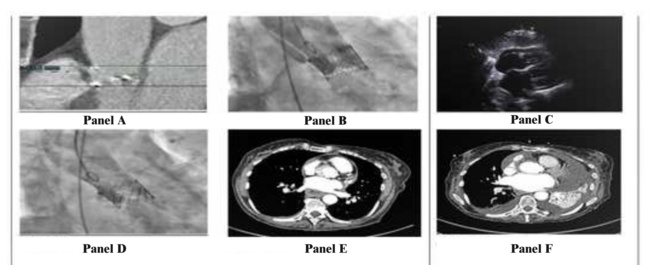

A 78-year-old woman with a background of hypertension and osteoarthritis presented with a history of syncope secondary to severe aortic stenosis. She underwent a computed tomography (CT) scan that showed a heavily calcific trileaflet aortic valve (Panel A). Her aortic annulus was measured at 445 mm2 with relatively modest aortic wall calcification. Following Heart Team discussion, she underwent a transfemoral transcatheter aortic valve implantation. A 26 mm Sapien S3 Ultra valve (Edwards Lifesciences) was deployed under rapid pacing. The patient reported chest pain extending to her back associated with a drop of blood pressure to 78/50 mm Hg. A check aortogram revealed an acute aortic dissection starting from the top frame of the transcatheter heart valve (Panel B). An echocardiogram revealed 0.8 cm of pericardial effusion with no evidence of right ventricular diastolic compromise (Panel C). In preparation for emergency open aortic repair, the patient became hemodynamically stable with no further chest pain. A repeat aortogram revealed that the dissection flap is no longer visible and likely to have sealed itself (Panel D). The patient was subsequently transferred for an urgent CT scan, which confirmed an ascending aortic dissection of 8.5 cm with no communication between the true and false lumen (Panel E). A conservative approach was elected, with the on-call cardiothoracic surgical team on standby if any change occurred in symptoms or hemodynamic, echocardiographic, or CT appearance. She was commenced on intravenous labetalol and was transitioned to oral antihypertensive, aiming for systolic blood pressure of less than 110 mm Hg. A repeat CT a few days later confirmed the dissection flap had not progressed (Panel F) and the patient was discharged home.